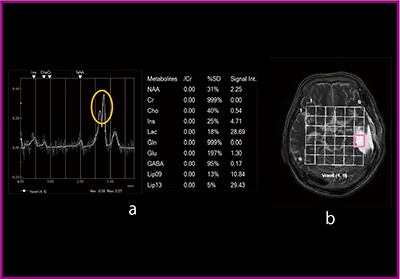

●MRS

MRスペクトロスコピー(MRS)は,体内のごくわずかな代謝物の信号を検出して周波数解析することで,スペクトルで生化学情報をとらえることができる。ECHELON OVALには,コンソール上で簡単に操作できる“ワンクリックMRS/CSI”と解析ソフトウエアであるLC-Modelが採用されている。

MRSによる代謝物の分布を二次元的に計測してカラーマップ表示するのがchemical shift imaging(CSI)である。転移性脳腫瘍の症例(図3)では,指定されたボクセル(b)のスペクトログラム(a)を見ると,正常でピークを示すコリン(Cho),クレアチン(Cr),NAAが抑制され,ラクテート(Lac)がピークとなる脳腫瘍の典型的な所見が示されている。

なお当院では,シングルボクセルのMRSや,左右対称に計測・解析を行うデュアルボクセルのMRSも行っている。

図3 MRSのCSI解析